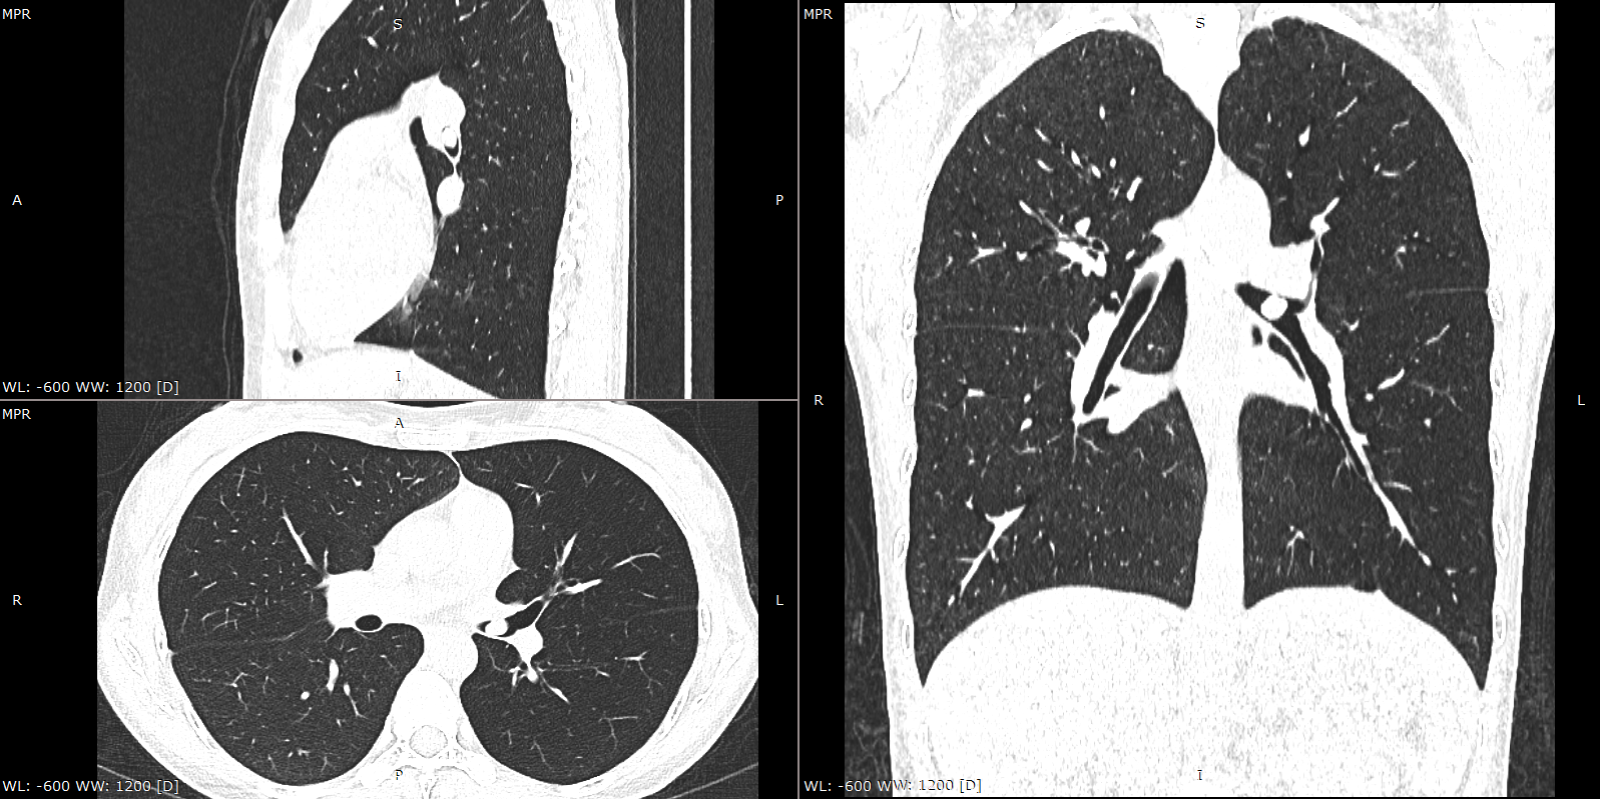

左主支气管结节

两年前38岁的王女士健康体检,发现左主支气管7×10mm结节,遂到我院就诊,支气管镜检查见左主支气管内带蒂结节,表面光滑。经支气管镜使用圈套器完整切除结节,结节根部冷冻冻融治疗。病理提示为低度恶性的类癌。近日复诊,胸部CT、支气管镜检查均未见肿瘤复发。

肺结节通常在肺实质、肺外周,支气管内结节为其特殊类型,不仔细阅片的话容易漏诊。病变除了常见的支气管肺癌,还包括低度恶性或良性的肿瘤。良性肿瘤可考虑支气管镜下直接切除,恶性肿瘤还是首选外科切除。王女士的病灶在左主支气管下段,紧挨上下叶开口,外科手术创伤大,而带蒂病灶又基本完整切除。最终王女士选择了继续随访方案。幸运的是,经过两年观察,未见复发。不过后续还要定期复查,以防万一。